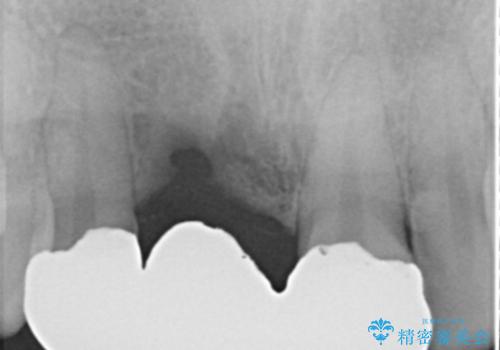

- 前歯ブリッジのやり変えを希望され来院された患者様です。

審美性を重視されていたので、オールセラミッククラウン(スペシャル)でのブリッジを選択されました。